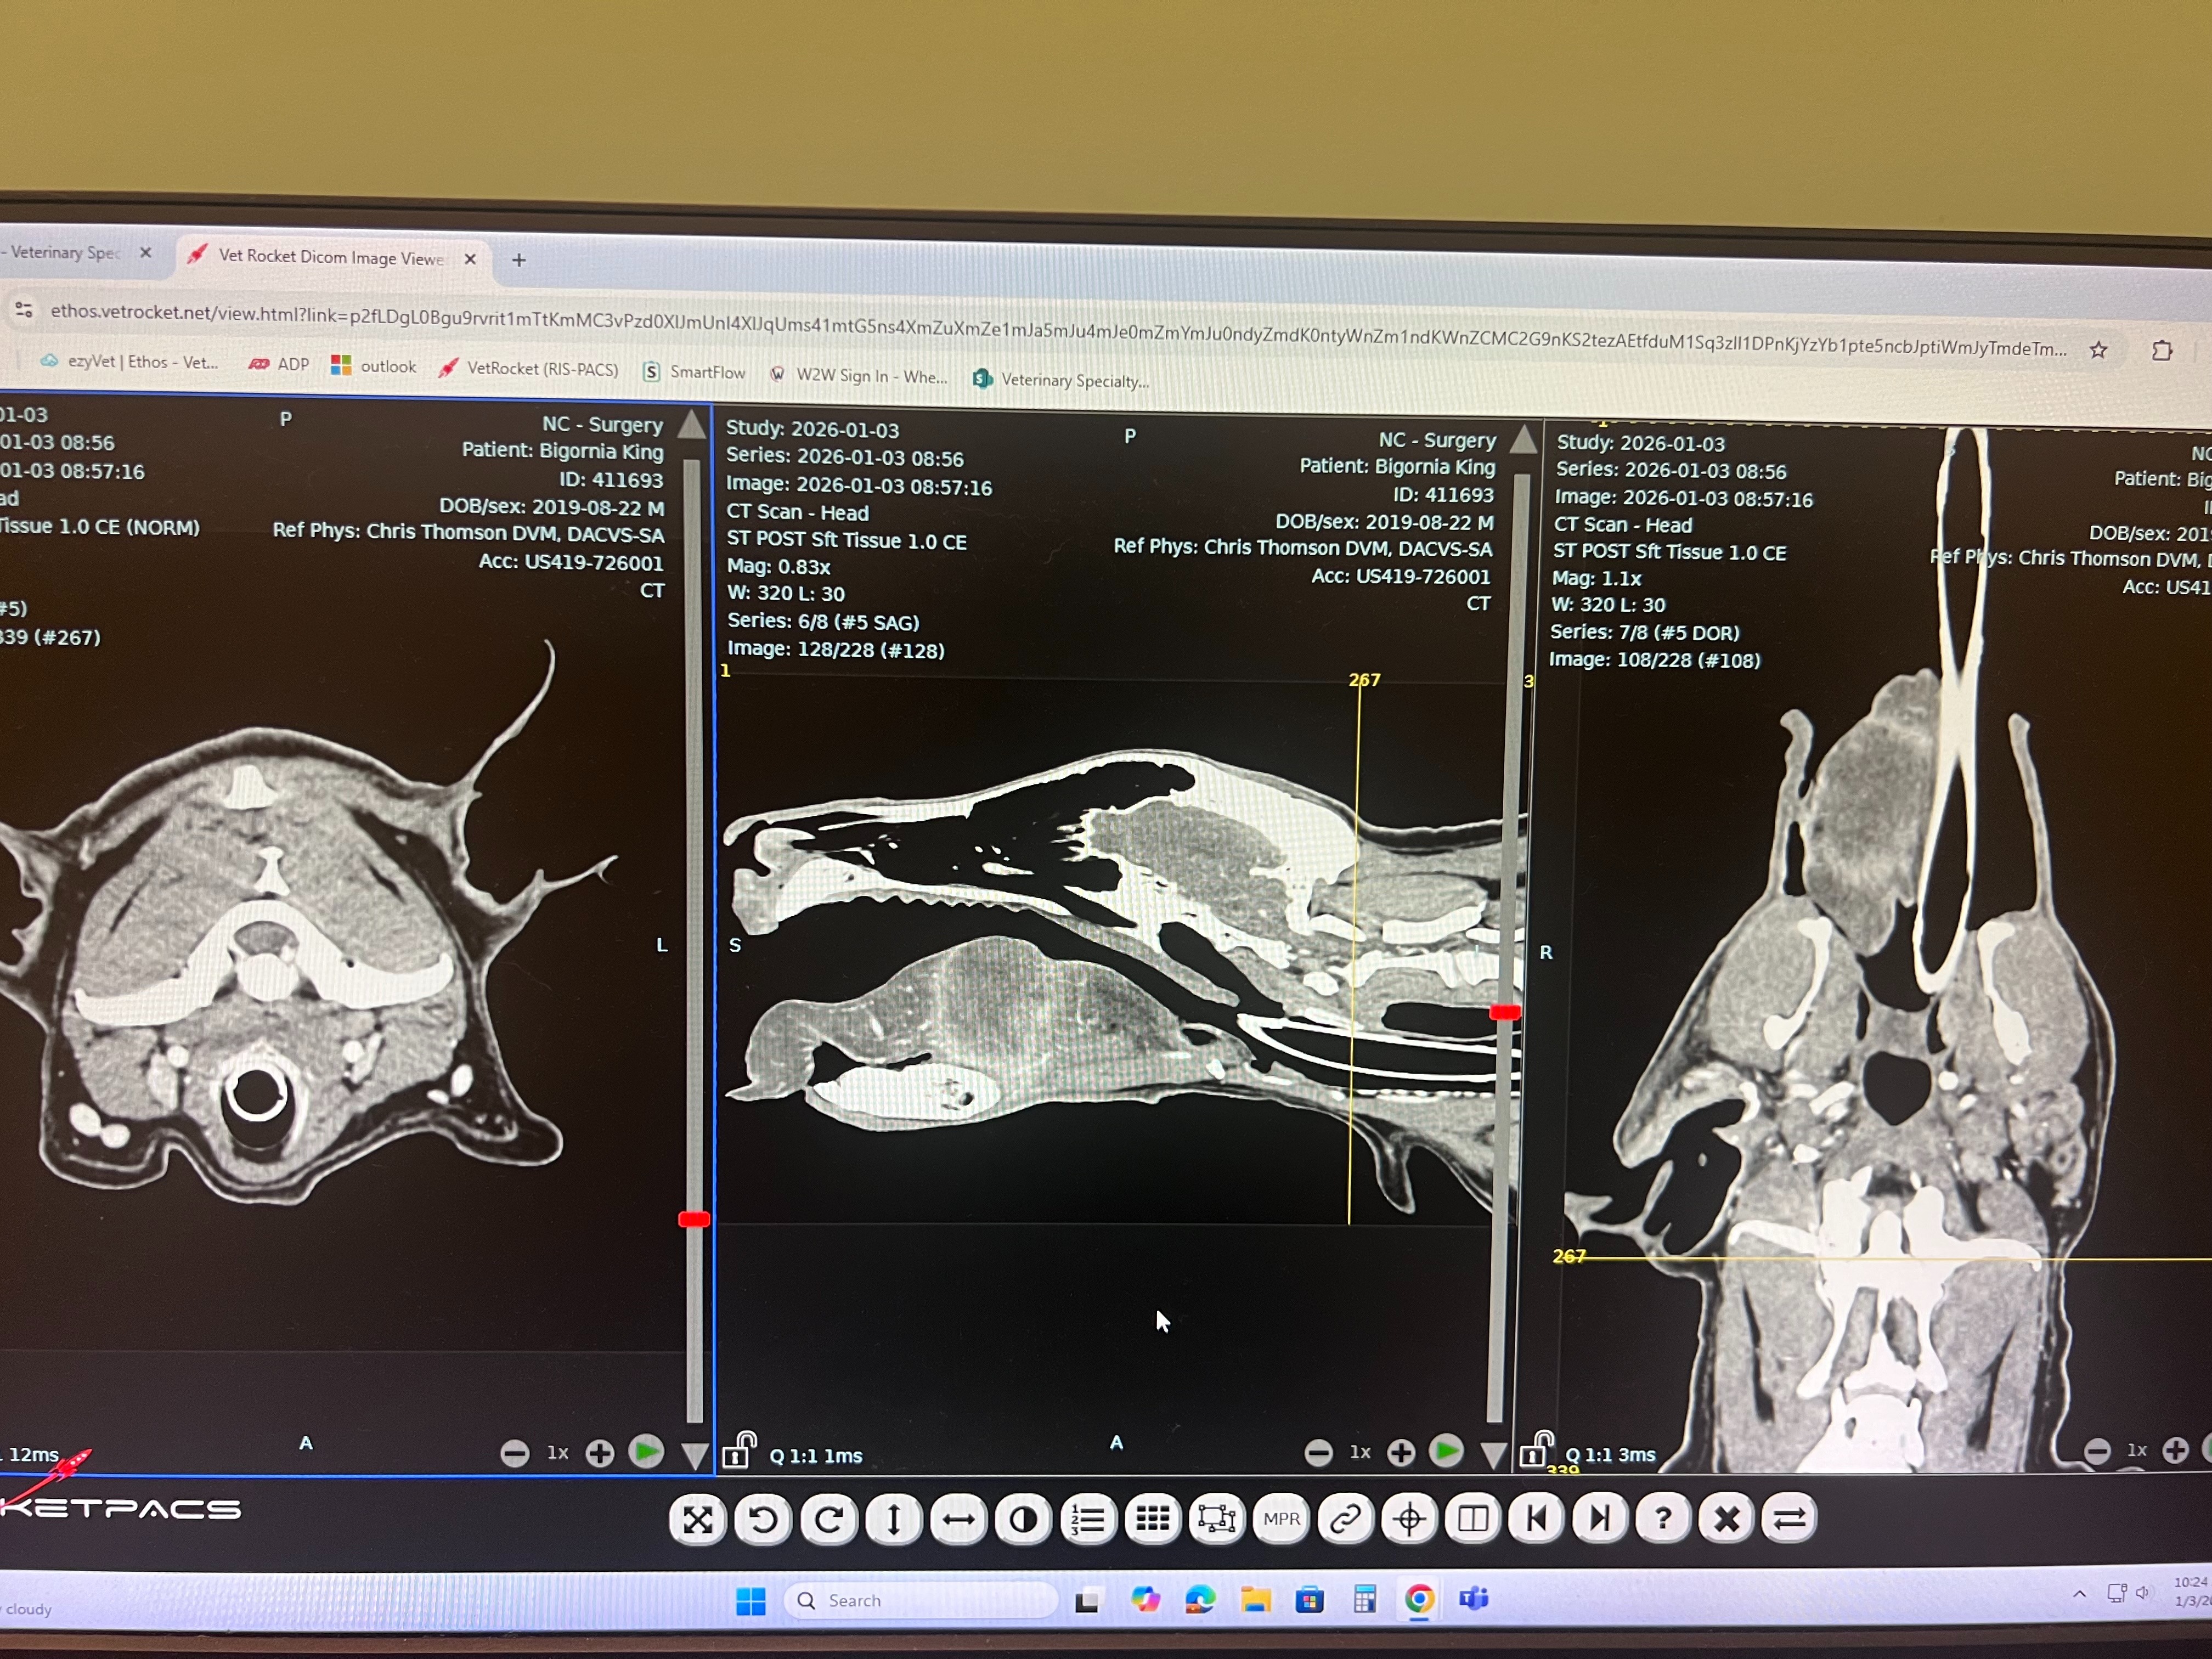

A CT scan was performed this morning, and there are 3 areas of concern: his ear has a large fluid-filled mass, his tongue has a large fluid-filled mass, and he also has a mass on his muzzle. The top rule-outs at this point are autoimmune disease, bacterial infection, or a fungal infection.